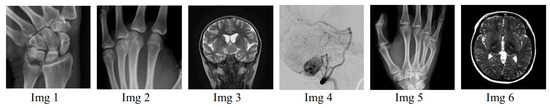

Figure 12. Grayscale medical images used in the test.

To assess the correlation between the original images with their encrypted–compressed forms, 4000 samples are arbitrarily selected from adjacent pixels in the test images (Figure 12), which are selected from the dataset in [59]. The results presented in Figure 13 and Table 2 show that the proposed scheme is able to break the existing correlation between adjacent pixels in the original images. This indicates that our scheme not only offers lossless compression, but also guarantees the low correlation between the pixels in its output images.

Figure 13. CC corresponding to the original Img 1–Img 6 (see Figure 12) and their compressed–encrypted versions, respectively.